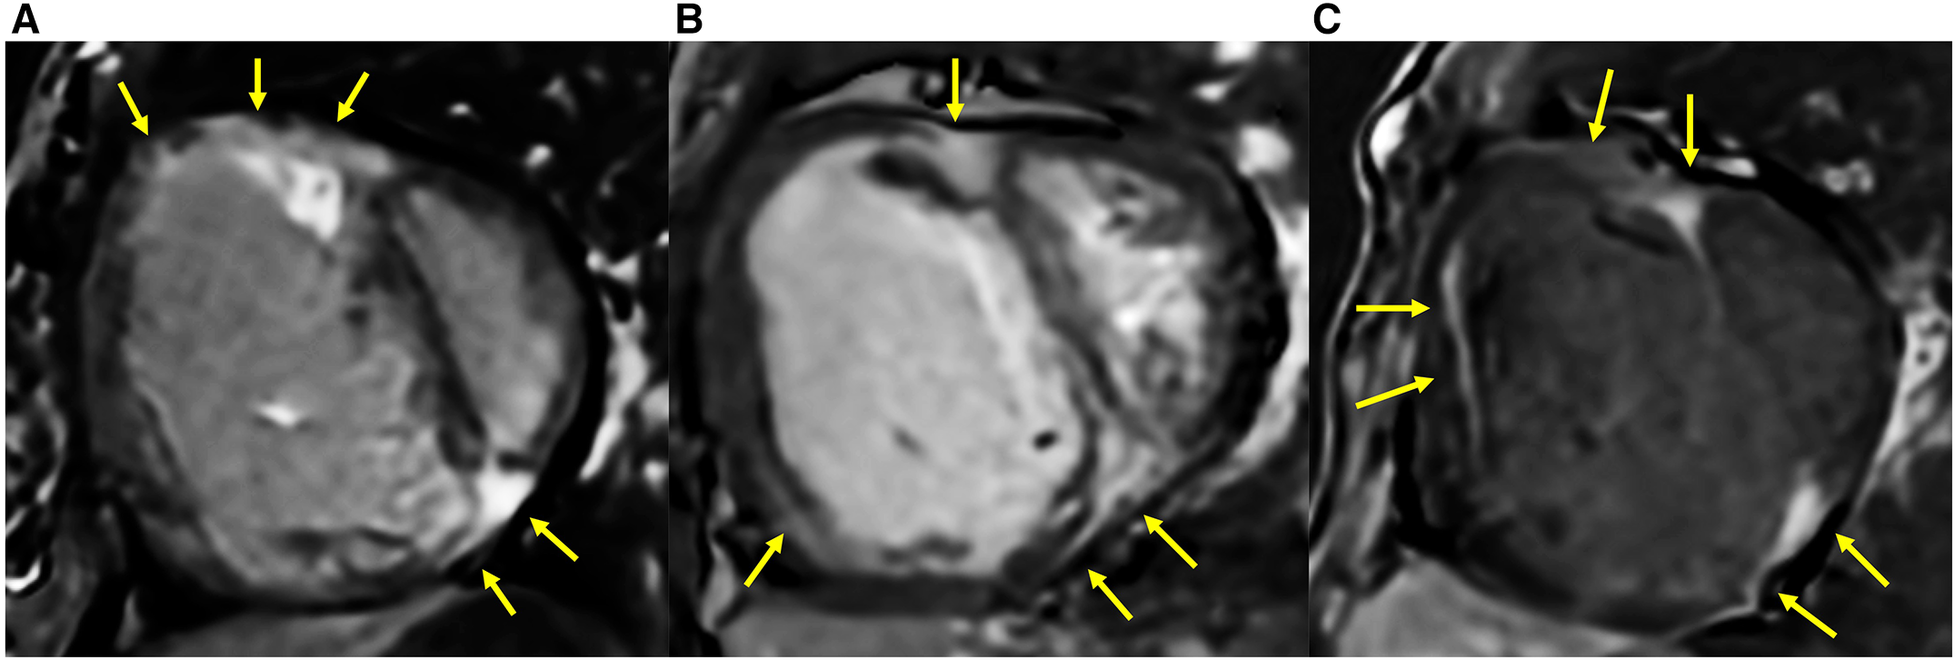

3.2 RV fibrosis in different groups

The comparison of RV fibrosis parameters between groups is listed in Table 2. The presence of LGE was identified in 94% of the population and 86% of the non-PH group (Figure 3), mostly located in the RVIP region. LGE in the septal and inferior RV region was predominantly observed in the ES group compared to the other groups (p = 0.031 and p < 0.001, respectively). Examples of LGE images from patients with ES are depicted in Figure 4. The mean LGE scores in the ES and PH groups were significantly higher than those in the non-PH group (p = 0.001). In terms of interstitial fibrosis, the ES group exhibited significantly higher native T1 and ECV values compared to those of the other groups (p < 0.001 and p = 0.037, respectively), predominantly occurring in the RVIP region. Examples of native T1 and ECV mapping for each group compared to cine and LGE images are shown in Figure 5.

Figure 4

LGE extended into the inferior RV and other parts of the RV free wall in ASD patients who had developed Eisenmenger syndrome (yellow arrow). (A) A 25-year-old female with mPAP of 70 mmHg, PVRi of 55.4 WU m2, PVR/SVR 1.5, Qp/Qs of 0.5, RVEF of 30%, systolic eccentricity index of 2.95, and SpO2 77%. (B) A 29-year-old female with mPAP of 48 mmHg, PVRi of 16.3 WU m2, PVR/SVR 1.1, Qp/Qs of 0.7, RVEF of 28%, systolic eccentricity index of 2.02, and SpO2 of 94%. (C) A 39-year-old female with mPAP of 65 mmHg, PVRi of 30.2 WU m2, PVR/SVR of 1.03, Qp/Qs of 0.8, RVEF of 18%, systolic eccentricity index of 3.8, and SpO2 of 70%.